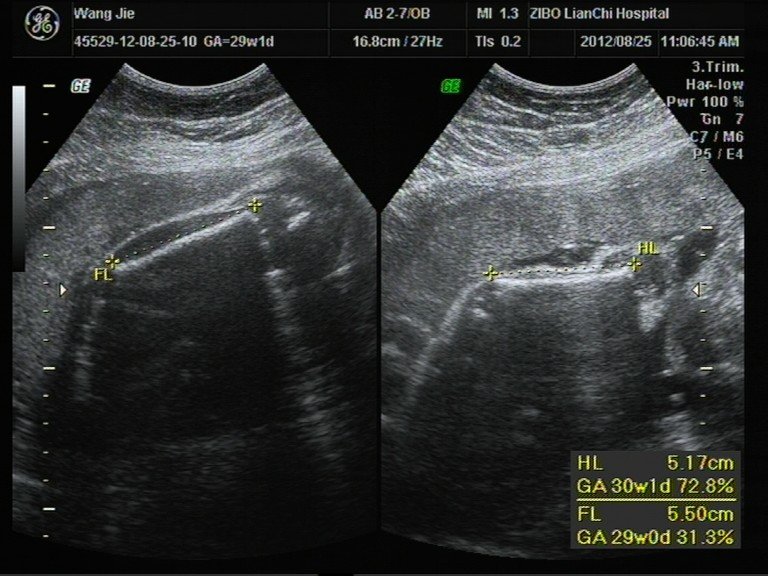

患者信息:女 29岁 病情描述(发病时间、主要症状等):彩超数据和相关照片,想知道宝宝男女。其余大部分照片在我百度空间的相册中。想得到怎样的帮助:想知道宝宝性别。曾经治疗情况及是否有过敏、遗传病史:四维彩超不清楚发哪张好。其余在我的百度空间中。

性别要3个月至B-。上面的列表中没有写这些。哦。怀孕孩子的性别是很好奇,以前我是在Web上确定什么样的B超单性别。有人说,胚胎又细又长的男性,短发女人。你看看数据,按照法官的话应该是个男孩。我是,但我不知道这是不是一个巧合。 这些都是很好玩,呵呵,不要把它看得太重。宝宝的健康是最重要的,什么样的性别...是相同的